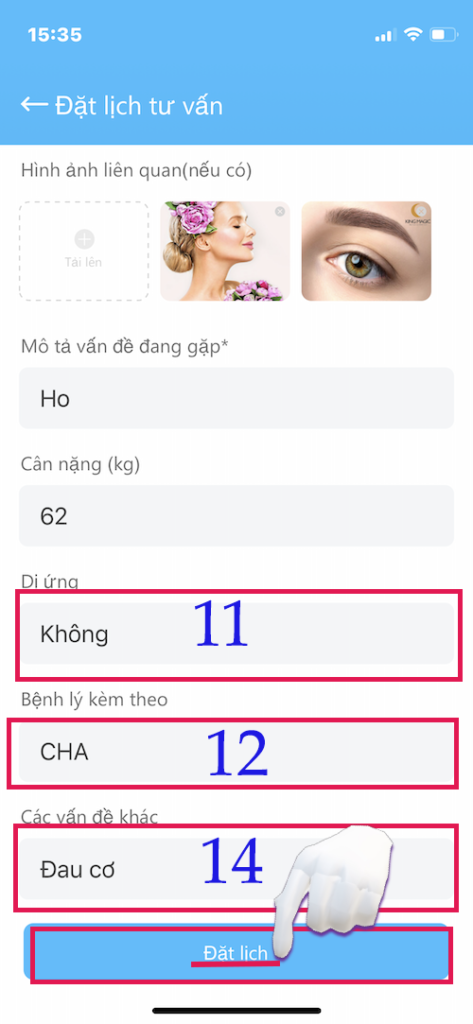

KHAI BÁO THÔNG TIN (tiếp theo)

Khai báo thông tin

- (11) Dị ứng (nếu có)

- (12) Bệnh kèm theo

- (14) Các vấn đề khác mà Bạn mắc phải

- Khai báo thông tin chính xác cho Bạn có điều trị tốt nhất.

- SAU CÙNG BẤM ĐẶT LỊCH

- Đặt lịch thành công khi các thông tin có (*) được điền và có đủ tiền trong tài khoản